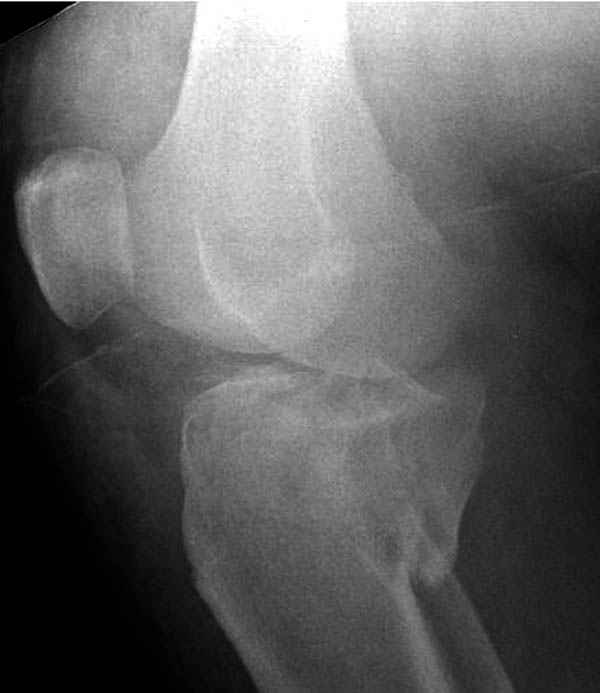

Трудно поверить, что разрекламированная Ортопедическая школа Восточной Украины позволяет такие странные снимки? На прямом снимке сохранен общий контур плато, но не известна судьба импрессии суставной поверхности. На полубоковой?, оставлен без репозиции задне-медиальный отдел, и навряд ли после такой фиксации можно удовлетвориться результатом.

Такая ситуация характерна для многих, когда принимается ошибочное решение, т.е пытаются фиксировать одним имплантом переломы двух мыщелков. Латеральная пластина приемлема только для тех случаев, когда сохраняется интактным медиальный диафизарный кортекс и отсутствует фрагментация на верхушке медиального перелома.

Представленные снимки не информативны, нужны отдельные качественные снимки коленного сустава и голени без ротации.